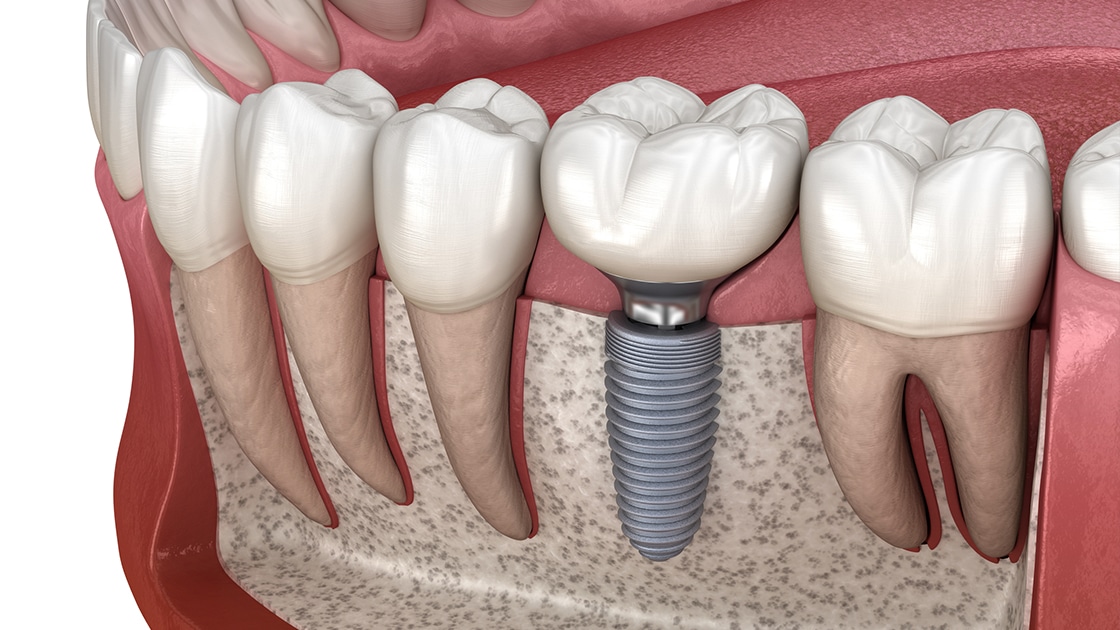

Dental implants are the Benchmark for modern-era tooth replacement, since they merge with your bone. Dental implants become a part of your smile by fixing damaged, or missing teeth with biocompatible screw-like devices mounted with crowns, bridges, and dentures to restore the missing teeth.

Although implanting Artificial teeth seems challenging, it’s still not as painful and frightening as it sounds. There are numerous advantages, including the following.